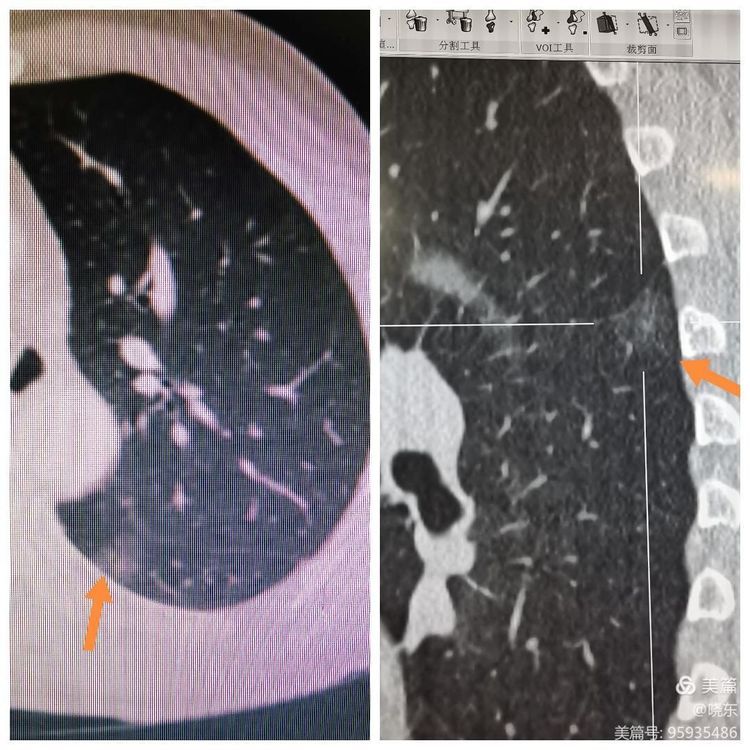

胸部CT提示左肺下叶背段GGO

术前CT引导下Hookwire穿刺定位